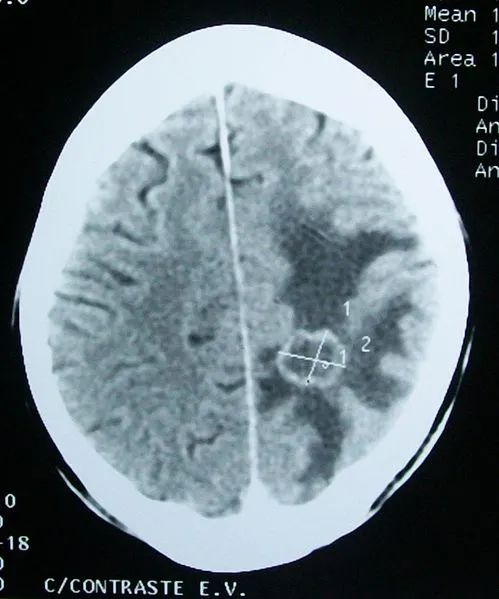

脑癌ct图片